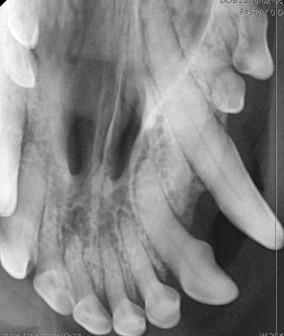

Dental Radiographs

We use advanced digital dental x-rays to gain a clear view of your pet’s oral health. This allows our team to detect hidden dental issues such as infection and design personalized treatment plans.